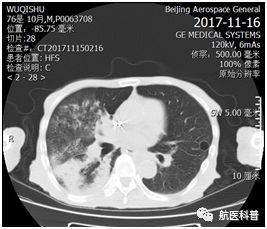

其中(zhong)一(yi)患者爲(wei)73歲男性,因“髮(fa)熱伴咳嗽1天餘”2017年(nian)11月15日(ri)入院,體(ti)重(zhong) 40kg、高(gao)1.65m、BMI 14.7kg/m2,患者1天餘前(qian)着涼後(hou)出現(xian)咳嗽、咳痰,爲(wei)黃色粘痰,伴髮(fa)熱,最高(gao)體(ti)溫37.5攝氏度,既往帕金森病史10年(nian),胃潰瘍行胃大(da)部(bu)切除術(shù)30年(nian),近2月體(ti)重(zhong)下降10公(gōng)斤,入院查體(ti)雙肺可(kě)聞及(ji)彌漫痰鳴音,白蛋白26g/L,聯(lian)係(xi)影像科(ke)緊急完善(shan)肺部(bu)CT可(kě)見右肺大(da)面積實變。